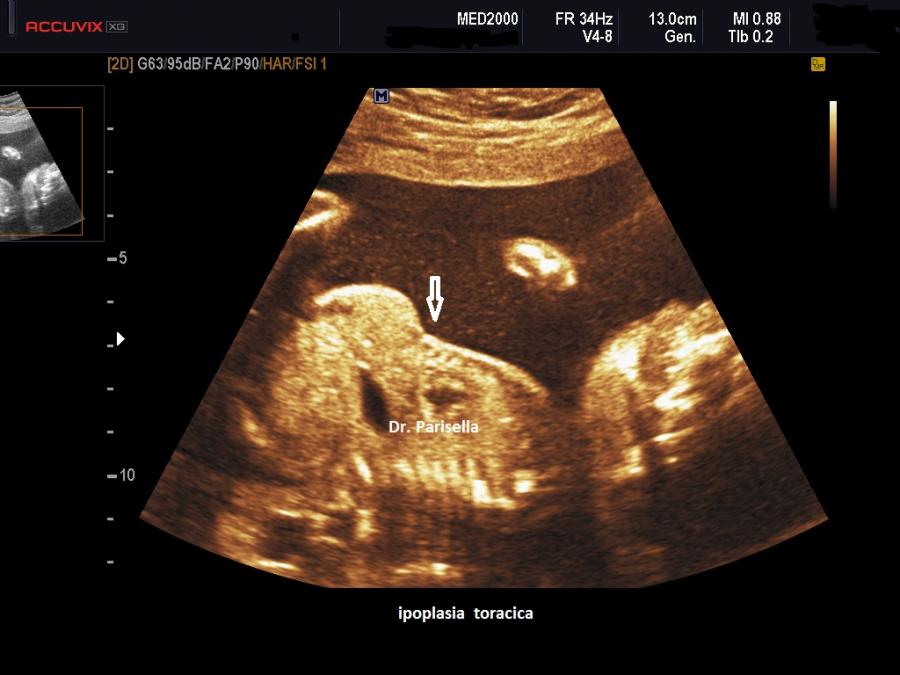

Osteocondrodisplasia di Blomstrand OMIM 215045

E' una displasia scheletrica autosomica recessiva caratterizzata da grave accorciamento di tutti i segmenti ossei degli arti, torace stretto con coste corte, protrusione della lingua (glossoptosi) dovuta alla cavità orale piccola, ipoplasia dello splacnocranio. Spesso si associa polidramnios.